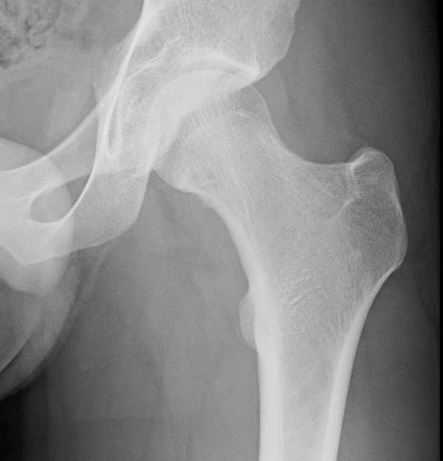

Xray

Shallow cortical defect on the surface of long bones

Periosteal chondromaXray periosteal chondroma